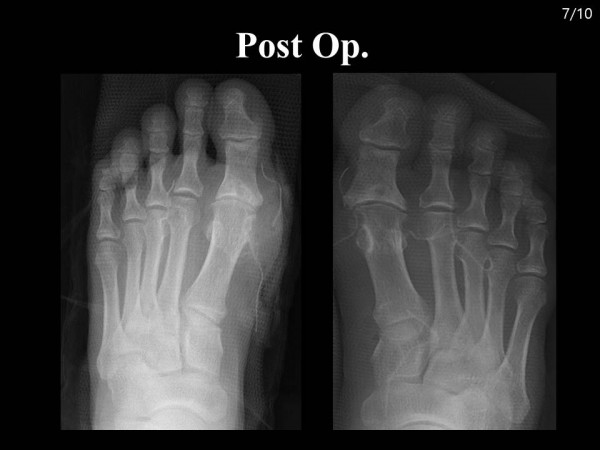

논문 및 학술활동 족부 양측 족부의 여러 부위에 동통성 종괴를 호소하는 58세 남자 환자 case report 20.08.24 15:33 1,798 양측 족부의 여러 부위에 동통성 종괴를 호소하는 58세 남자 환자 case report : 2018 대한족부족관절학회 춘계학술대회 양측 발 통풍성 결절로 내원한 환자 증례보고 이전글 Subtalar Arthroscopy and Posterior Endoscopy (거골하 관절경술 및 후방 내시경술) 20.08.24 다음글 족저 근막 파열 환자에서의 초음파 소견 20.08.24 목록